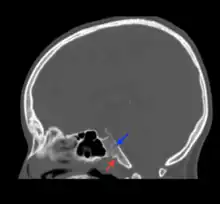

Fosas navicularis magna (red arrow) on mid-sagittal computed tomography

Fossa navicularis magna is located on the anterior surface or pharyngeal surface of the clivus. Its position when present is between the spheno-occipital synchondrosis and the foramen magnum. Size of this fossa varies considerably and its depth ranges from 3.49 to 4.94 mm.[3] A histological study reported the presence of loose connective tissue containing collagen and elastic fibers within the fossa navicularis magna.[4]